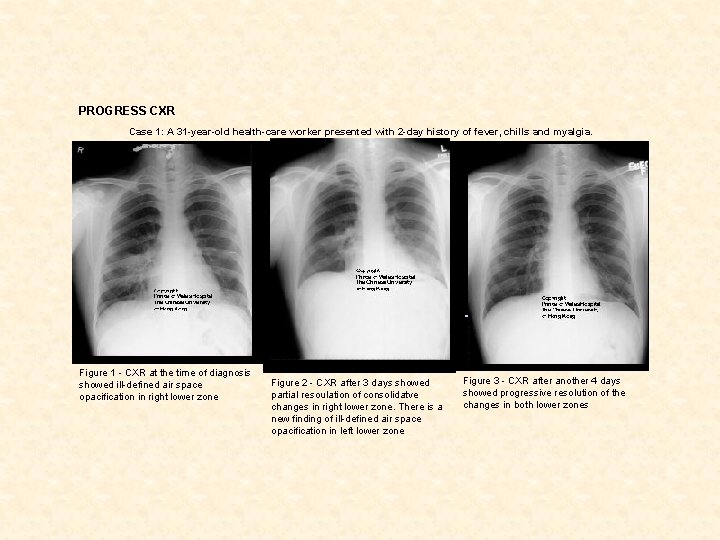

PROGRESS CXR Case 1: A 31 -year-old health-care worker presented with 2 -day history of fever, chills and myalgia. Figure 1 - CXR at the time of diagnosis showed ill-defined air space opacification in right lower zone Figure 2 - CXR after 3 days showed partial resoulation of consolidatve changes in right lower zone. There is a new finding of ill-defined air space opacification in left lower zone Figure 3 - CXR after another 4 days showed progressive resolution of the changes in both lower zones